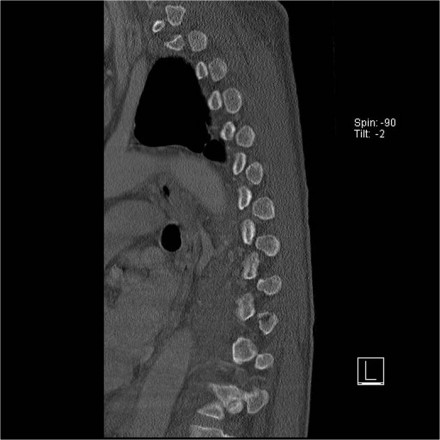

Case 4

Look at the images.

How would you describe the morphology and the PLC?

The findings are:

- Morphology: Distraction- 4 points

- PLC: always disrupted in distraction on posterior side - 3 points

- TLICS: 7 points